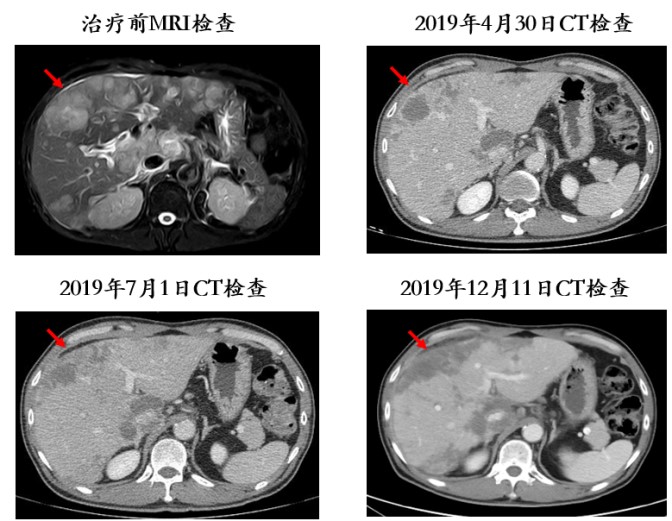

此后定期复查CT,显示门脉癌栓位于右支近汇合处,较治疗前明显退缩(图2);肿瘤灶较治疗前直径缩小,且乏血供,疗效评价为部分缓解(PR;图3)。

图2. 患者门脉癌栓较治疗前明显退缩